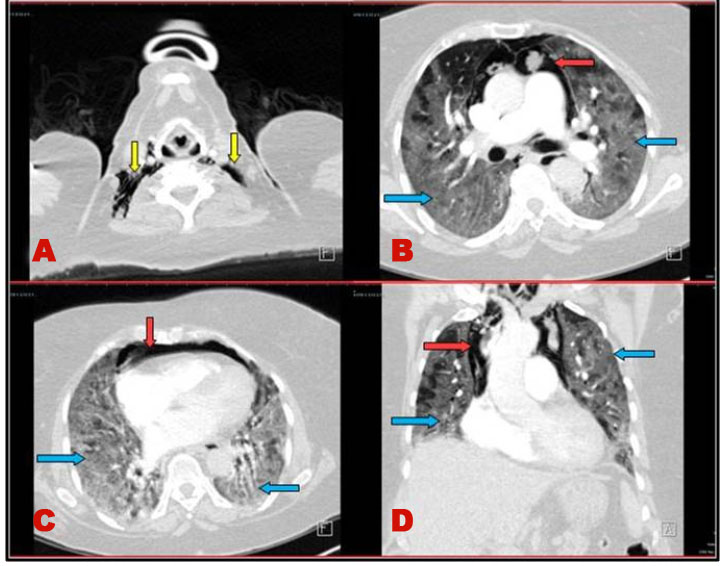

A 65-year-old female patient with medical past history of obesity (body mass index (BMI) at 35 kg/m2), hypothyroidism treated by levothyroxine replacement therapy, was admitted in pulmonology department for confirmed COVID-19 pneumonia with two weeks history of fever, chills, asthenia, dry cough, and progressive shortness of breath, with initial non-contrast chest computed tomography scan (chest CT scan) showing bilateral peripheral ground-glass opacities and crazy paving with estimated percentage of lung involvement at 10% (Figure 1). She was managed initially with oxygen-therapy with nasal prongs associated to antibiotics, dexamethasone 6 mg/12 h, anticoagulation, hydration, and vitamins. On day four of admission, the patient developed a rapid onset of retrosternal chest pain associated to a moderate acute respiratory failure with severe hypoxemia: oxygen saturation (SpO2) of 88% under 15 L/min of oxygen with a non-rebreather mask. In front of the worsening of her state, she was transferred to our intensive care unit (ICU). Upon admission, her respiratory rate (RR) was of 35 breaths/min with struggle signs and hypoxemia and soft-tissue crepitus bilaterally. She was conscious with stable hemodynamic state. Laboratory tests revealed an elevated C-reactive protein (CRP) concentration of 53 mg/L (reference:<5 mg/L). Complete blood count showed a leukocytosis of 11.8×109/L (reference: 4–10×109/L), with lymphopenia (0.4×109/L). She had hepatic cytolysis with alanine aminotransferase (ALAT) and aspartate aminotransferase (ASAT) at 100 IU/L (reference:<45 IU/L) and 68 IU/L (reference: <50 IU/L) respectively. Serum level of D-dimer was at 457 µg/L (reference:< 500 µg/L). Arterial blood gas (ABG) showed a pH:7.41, PaCO2:43 mmHg, PaO2:74 mmHg, HCO3:27 mmol/L and PaO2/FiO2 ratio at 205. A contrast-enhanced chest CT scan was performed showing diffuse lower neck subcutaneous emphysema associated with diffuse PM and diffuse bilateral ground-glass opacities with posterior and peripheral predominance associated to alveolar consolidation with estimated percentage of lung involvement at 90% consistent with critical COVID-19 pneumonia (Figure 2A, Figure 2B, Figure 2C, Figure 2D). Urgent mediastinal decompression with chest drainage tube wasn’t immediately indicated in front of the maintained stable hemodynamic state, so we decided the conservative therapy with reduced airway pressure with non-invasive ventilation (NIV) [pressure support (PS) of 12–14 cmH2O, positive end expiratory pressure (PEEP) of 4 cmH2O, and fractional inspired oxygen (FiO2) of 100%]; awake prone positioning and close monitoring. Initially we obtained a slight improvement of his respiratory state. At day 7 of ICU stay she was intubated in front of NIV failure. The patient was ventilated with protective ventilation with volume assist-control ventilation mode (VAC mode) [tidal volume (Vt) at 6 mL/kg predicted body weight (PBW), PEEP at 4 cmH2O: low level in front of the PM, respiratory rate at 30 breaths/min and 100% of FiO2. She was immediately put under continuous infusion of sedation and neuromuscular blockers. Despite protective ventilation with lower pressure, there was a maintained severe hypoxemia, and the patient passed away due to refractory hypoxemia few hours later.

Figure 2: (A–D) Contrast-enhanced chest CT scan showing lower neck subcutaneous emphysema (yellow arrows), diffuse pneumomediastinum (red arrows), and diffuse bilateral ground-glass opacities (blue arrows).